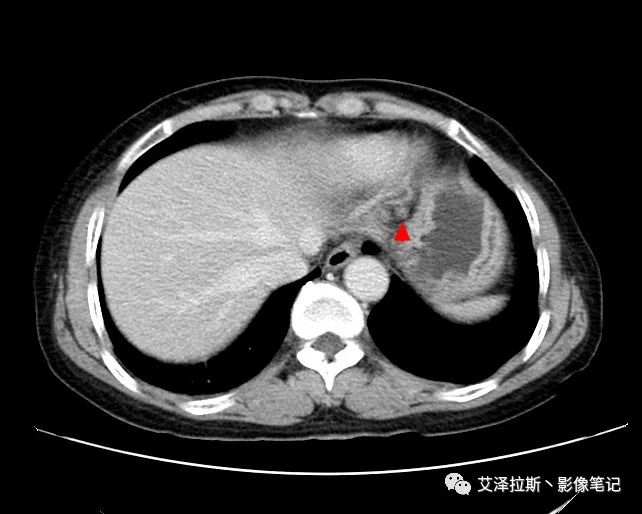

圖2 腫瘤

【影像所見】 胃竇部狹窄,胃壁環形增厚,小彎側見一巨大潰瘍,周圍伴“環堤征”,漿膜面不完整,胃周脂肪見網格狀條索影,病灶與肝臟左葉、胰腺鉤突脂肪間隙消失,增強掃描病灶明顯強化。引流區內約15個區域淋巴結受累。

【診斷意見】 胃竇部胃癌(T4N3期) 該病例腫塊突破漿膜層,與肝臟左葉、胰腺鉤突分界不清,脂肪界面消失,定為T4期; 受累及的淋巴結為15個區域,定為N3; 有無遠處轉移尚不明確,所以M期暫時無法確定。